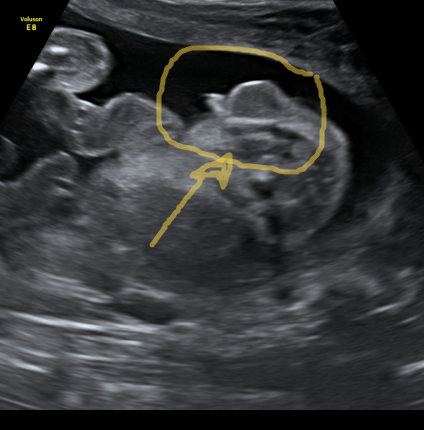

И как вы что понимаете на этих черно-белых непонятных картинках )) я на УЗИ даже на экран не смотрю, потому что ничего не вижу и не понимаю)))

У нас экраны большие перед кушеткой висят и узисты прям стрелочкой показывают)) А здесь вверху справа прям бугорок с писюном торчит, даже не прячет))

Мужчина, мальчик, сыночек) Это круто, и со средним разница маленькая! Мошонку, извини, не увидела))) Вообще не понимаю, как узисты что определяют. Я попу от головы не отличу, кажется))

Смотри справа вверху бугорок с писюном))) Я к Платко ходила, он все стрелочкой показывал и подробно рассказывал.